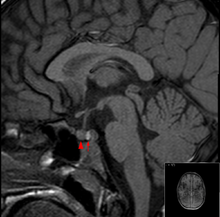

Hypophyse in der MRT (T1, nativ): Der Pfeil zeigt auf die Neurohypophyse (signalintens/hell), der Pfeilkopf auf die Adenohypophyse.